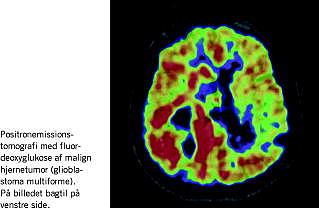

Som disse linjer skrives er ansøgninger om midler til disse projekter netop afsendt, og endelig er vi på tærsklen til en gennemgribende og for de enkelte specialer endnu ukendt omstrukturering af sygehusvæsenet. De beslutninger, der tages i denne forbindelse, er naturligvis af afgørende betydning for de nævnte projekter (Figur 1 ).